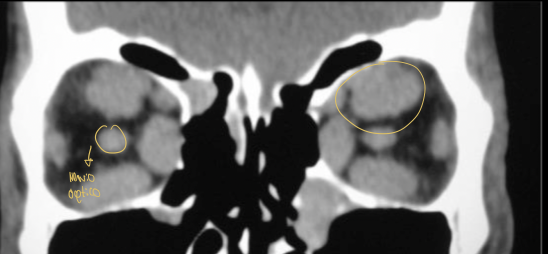

Hallazgos que podemos encontrar en una TC de orbitopatía tiroidea

• Agrandamiento de los músculos extraoculares

• Áreas de baja densidad debido a depósitos de glucosaminoglicano

• Exoftalmos

• Nervio óptico estirado

¿qué enfermedad sospechas?

orbitopatía tiroidea